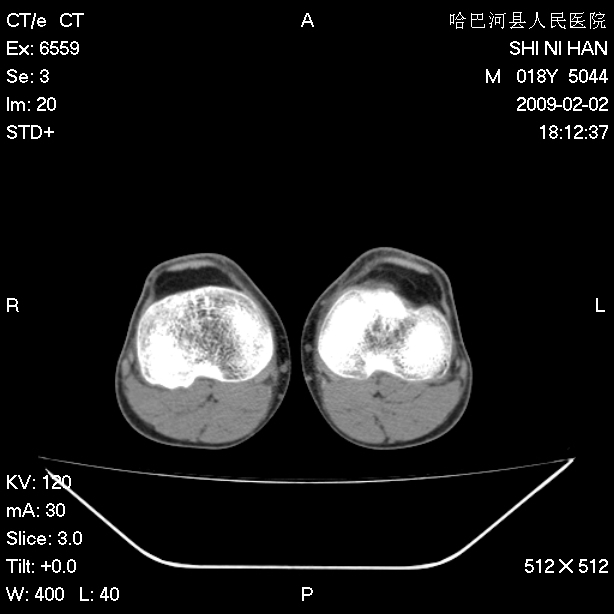

标题: CT17889:外伤后右膝关节反复疼痛3年余 [打印本页]

标题: CT17889:外伤后右膝关节反复疼痛3年余

ct未见明显异常。关节腔未见明显积液,半月板未见明显撕裂。但最好还是mri看看韧带及半月板情况。